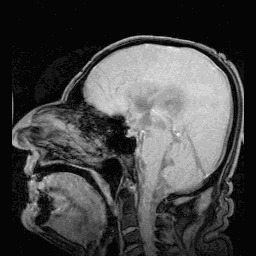

09核磁共振下,脑脊液随心跳搏动